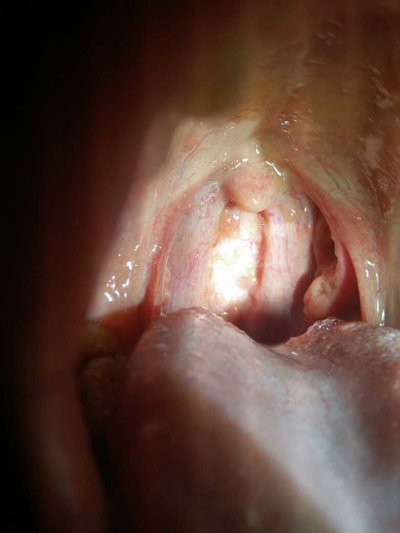

Cough yellow green sputum shows purulent inflammation in the body, that is, respiratory tract infection with tracheitis or bronchitis and other diseases, which is mainly caused by pneumococci, but also has a great relationship with pneumonia. Cough yellow green sputum is the most common kind of purulent bacteria, which will appear purulent and white blood cell necrosis tissue after infection.

The color of the cough is different, which means that the disease is different. From the expectoration we can see what kind of disease we have. The yellow green sputum is caused by respiratory tract infection, which has a lot to do with the diet. In daily life, patients with yellow green sputum should pay attention to keep warm.

Cough, expectoration and throat discomfort are symptoms of respiratory diseases. Cough out is yellow phlegm is caused by wind heat cold, can drink some special treatment of wind heat cold drug treatment. Usually more like to eat spicy food, we must pay attention to, long time to eat spicy food will also cause cough and expectoration.